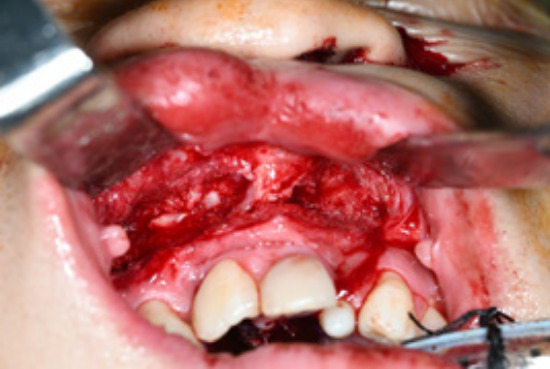

The ultimate goal of cleft palate repair is to achieve an intact palate with the separation of the oral and nasal cavities. However, some patients develop an oronasal fistula in the secondary palate after palatoplasty. Postoperatively, a secondary palatal oronasal fistula may develop, leading to functional problems. In this study, we describe a patient with recurrent oronasal fistula and alveolar cleft with multiple failed previous reconstructions at another clinic. The oronasal fistula and alveolar cleft were repaired using a tongue flap and an iliac bone graft, respectively. The patient demonstrated excellent clinical progress with no recurrence of the oronasal fistula at the 1-year follow-up.